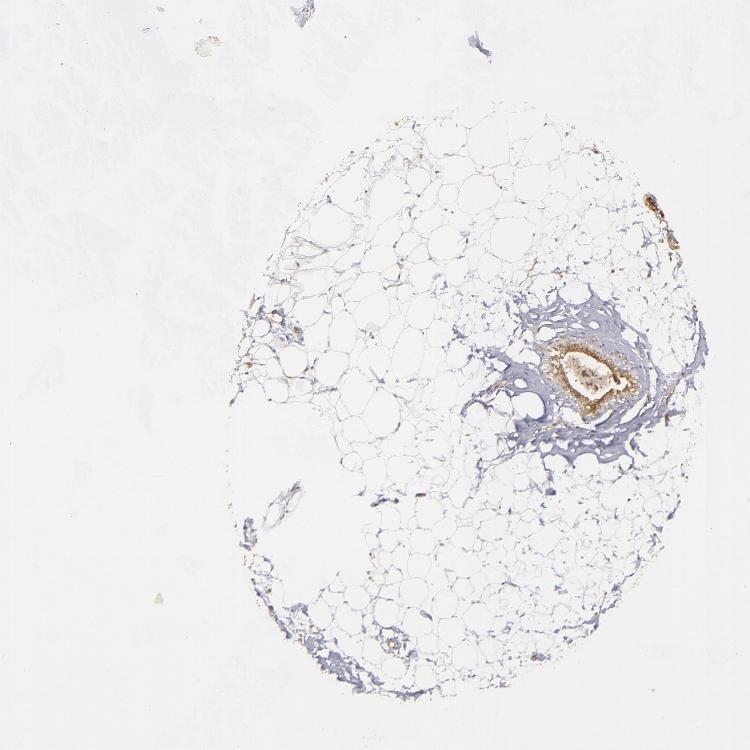

ADIPOSE TISSUE - Antibody stainingi

Antibody staining in the annotated cell types in the current human tissue is reported as not detected, low, medium, or high, based on conventional immunohistochemistry profiling in selected tissues. This score is based on the combination of the staining intensity and fraction of stained cells.

Each image is clickable and will lead to virtual microscopy that enables deeper exploration of all samples and also displays staining intensity scores, fraction scores and subcellular localization as well as patient and tissue information for each sample.

Antibody HPA002935

Adipocytes Medium